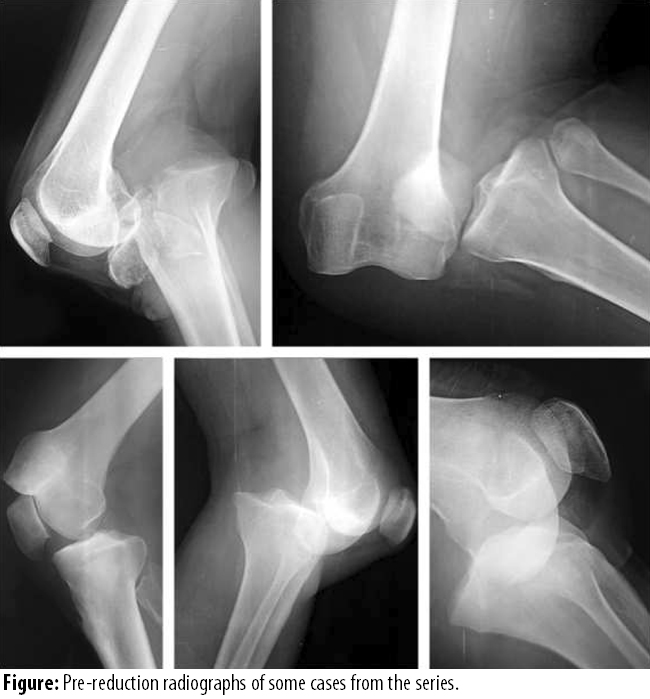

After receiving patient in ED and following initial trauma protocols, standard posterior anterior and lateral radiographs of the affected knee were taken (Figure).